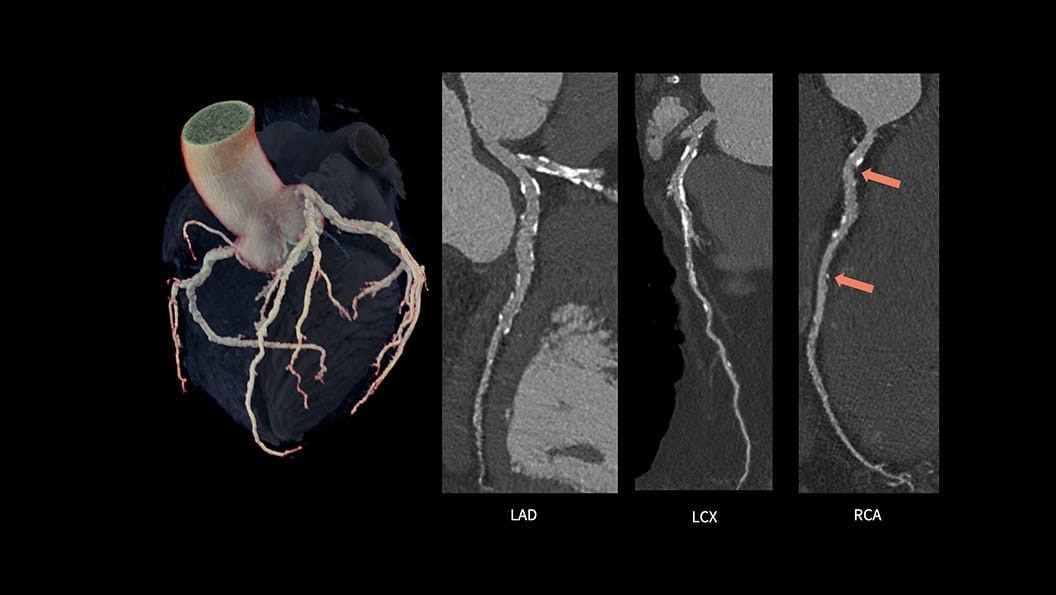

CardiQ Suite

An integrated suite of CT Cardiac post-processing tools, built for automation and workflow efficiency.

Consistency

>90% concordance with CACS‑DRS classification grouping⁵

Identification

>95% correct identification of the presence of coronary artery calcifications⁵

Labeling

>90% accurately labeled coronary artery territories⁵